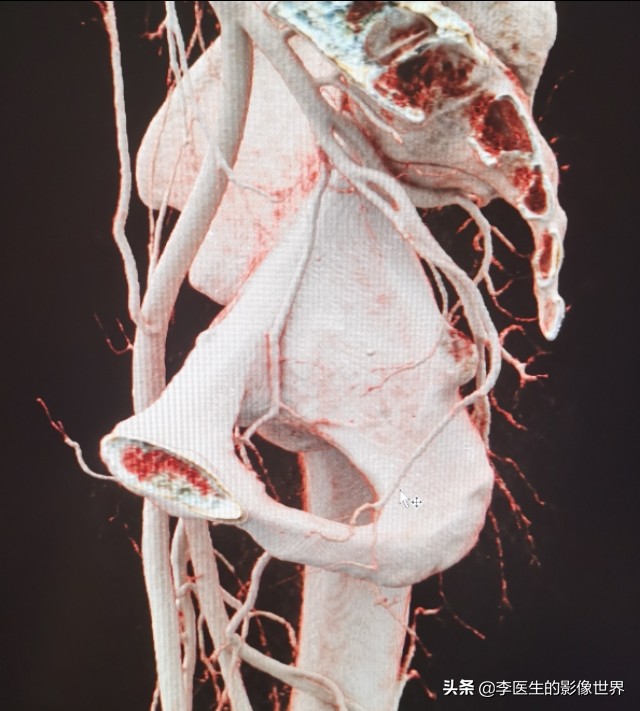

右侧阴部内动脉显示清晰,分出YJ动脉、会阴动脉。

右侧阴部内动脉显示清晰,分出YJ动脉、会阴动脉

鼠标所指左侧YJ动脉狭窄、显示不清。

鼠标所指左侧YJ动脉狭窄、显示不清。